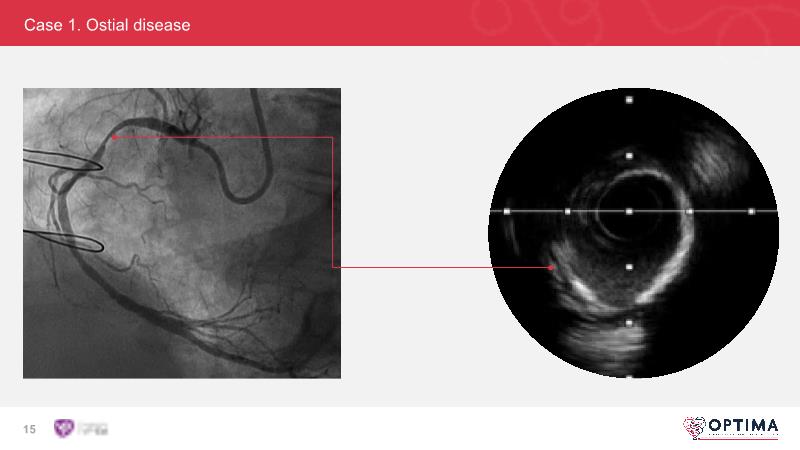

Cracking calcium: intravascular lithotripsy’s unique mode of action in treating calcified lesions – What's the evidence?

Watch this GulfPCR-GIM 2022 session to understand the unique mechanism of action of IVL, the use of intravascular imaging in calcium identification, the gender gap, disrupted CAD trials, and the evolution of treatment of calcified lesions together with the role of IVL.

- To be familiar with intravascular lithotripsy and its unique mechanism of action and the use of intravascular imaging in identifying calcium